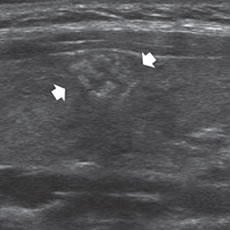

Un nódulo que tiene un componente quístico significativo, usualmente es un nódulo benigno hiperplástico, que ha acumulado abundante coloide (Figura 2a) o bien, un nódulo sólido que ha experimentado un proceso de degeneración colicuativa o hemorragia (Figura 2b). El coloide o el contenido líquido de un nódulo se ve anecogénico (negro en la imagen ecográfica) y las estructuras sólidas se ven ecogénicas (distintos tonos de grises), siendo la ecogenicidad similar al del parénquima tiroideo. En un nódulo sólido la ecoestructura y la ecogenicidad pueden ser variables. En general, la frecuencia de carcinoma es muy baja en nódulos quísticos13 y la mayoría de los carcinomas se presentan como nódulos sólidos (Figura 2c).

Figura 2. a) Quiste coloideo anecogénico y focos ecogénicos (flecha) con artefacto en cola de cometa; b) Nódulo mixto sólido-quístico (cabezas de flechas). Imagen vegetante (flecha) adherida a un tabique que se proyecta al lumen; c) Comparación entre el aspecto ecográfico de un cáncer papilar sólido (flecha abierta) y un quiste coloideo anecogénico.